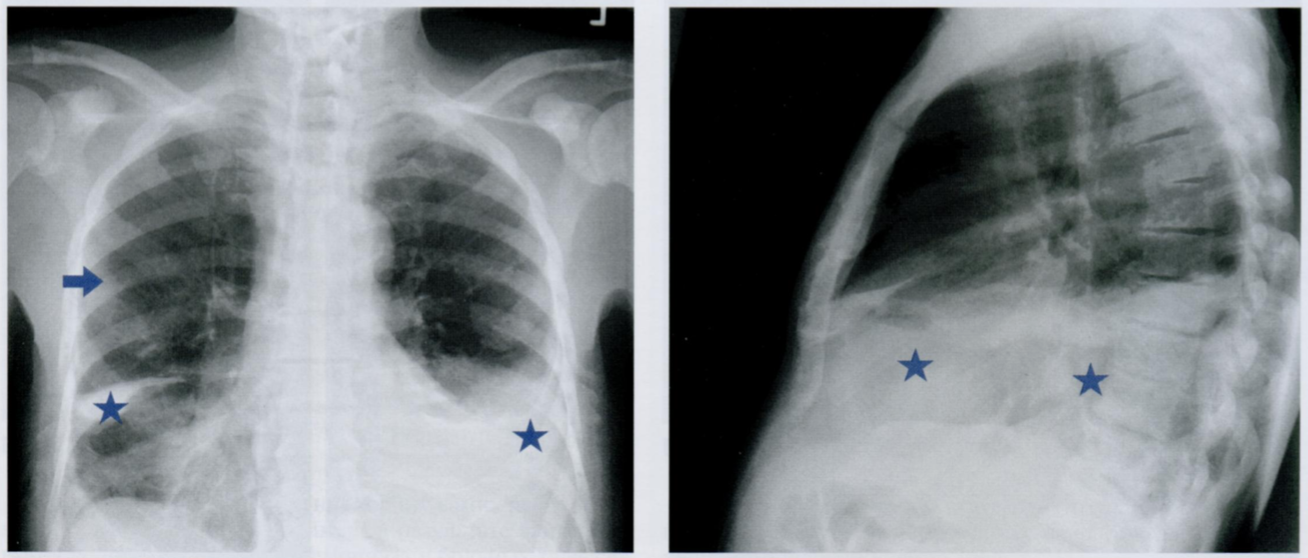

Внимательно рассмотрите снимок с метастазами (стрелочка) и плевральным выпотом (звездочка). Это случай поздней стадии рака. Оцените позвонки в БП.

Попытайтесь определить тип метастаза и предопложить источник первичной опухоли.

Помним про остеобластические, остеолитические и смешанные метатсазы.

На снимке представлен пример распространенного метастазирования в кости при раке предстательной железы в далеко зашедшей стадии.

Мы видим генерализованное диффузное увеличение рентгеновской плотности костей. Посмотрим на боковую проекцию, оценим позвонки. Такой позвоночник называют “с позвонками из слоновой кости”.

Стрелочкой отмечен изолированный очаг остеолиза. Такой смешанный литико-бластический тип метастазирования характерен для рака предстательной железы, молочной железы и опухолей ЖКТ. Звездочкой отмечен плевральный выпот.